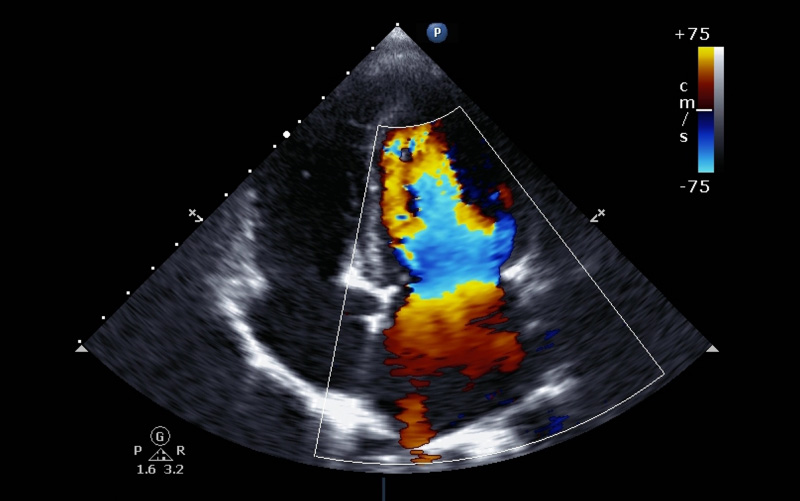

Toni C. Wild knew hair loss, fatigue and nausea were common side effects of the chemotherapy drugs she needed to treat her breast cancer. She wasn't prepared for heart failure.